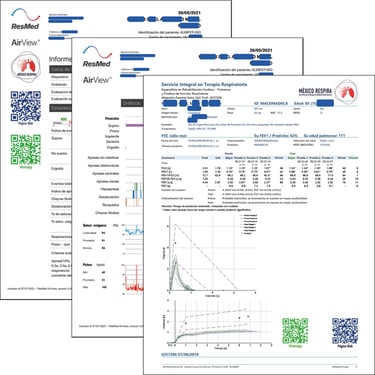

Tenemos pruebas especializadas en el diagnóstico de enfermedades pulmonares o respiratorias para iniciar tratamiento, evaluar la evolución del padecimiento o tratamiento y/o para iniciar o regular un programa de rehabilitación pulmonar.

Contamos con laboratorio respiratorio, haciendo pruebas de función pulmonar, médicos especialistas, enfermeras, terapeutas físicos, terapeutas respiratorios, terapeuta de deglución, materiales y equipo médico de última generación.